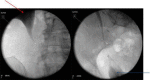

Ureteric strictures can be caused by traumatic pelvic surgery, urolithiasis and instrumentation. There are various treatment options for ureteric stricture, including laparoscopic ureteric reimplantation. A 56-year-old female with a history of chronic left pelviureteric junction obstruction presented with urosepsis secondary to right-sided urolithiasis. The patient had a left nephrectomy and developed right-sided ureteric stricture following repeated ureteroscopy to manage her stone disease. The treatment with ureteric stenting was unsuccessful. Here we present a case on the feasibility of laparoscopic reimplantation for ureteric stricture in a solitary kidney to preserve renal function and avoid further ureteroscopy or nephrostomies.